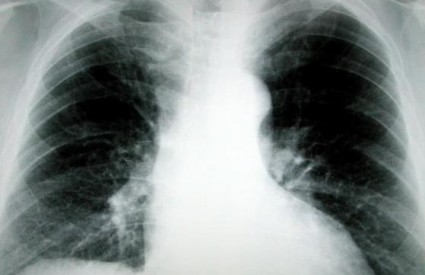

Rak pluća postat će izlječiv?

"Upravo smo završili veliku studiju koja je trajala tri godine. Do sada o tome nisam smio pričati, ali nisam niti htio izlaziti u javnost o stvarima koje nisu bile sto posto sigurne. Sada sa sigurnošću mogu reći da za šest do dvanaest mjeseci izlazimo u javnost s lijekom protiv najčešćeg oblika karcinoma pluća, a to je karcinom pluća nemalih stanica koji je uzrokovan mutacijama u proteinu EGFR. To je jedna predivna vijest za oboljele od karcinoma pluća od kojeg u svijetu umre godušnje 1,6 milijuna ljudi", rekao je Štagljar.